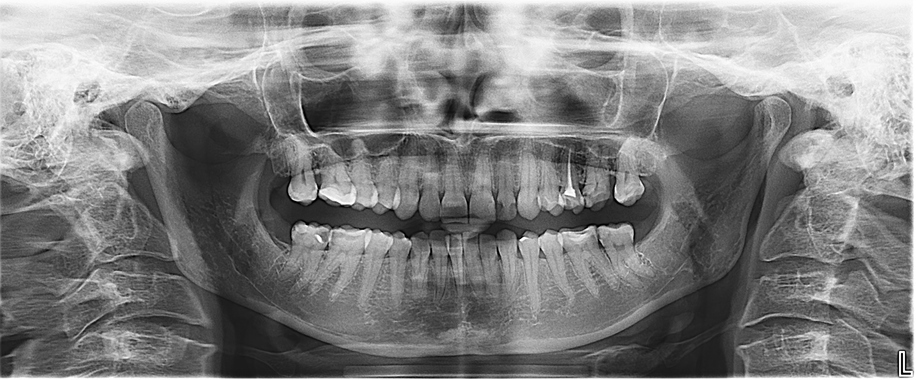

How One Leading DSO Used Analytics to Drive a 26% Increase in Crown Treatment Planning Rates

[Sponsored] A recent webinar sponsored by Overjet offered insights from Affinity Dental Management executives on how AI-driven clinical intelligence software can transform DSOs.